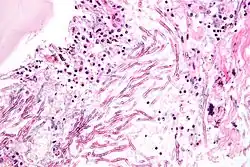

| Micrograph showing a mycosis (aspergillosis). The Aspergillus (which is spaghetti-like) is seen in the center and surrounded by inflammatory cells and necrotic debris. H&E stain. | |